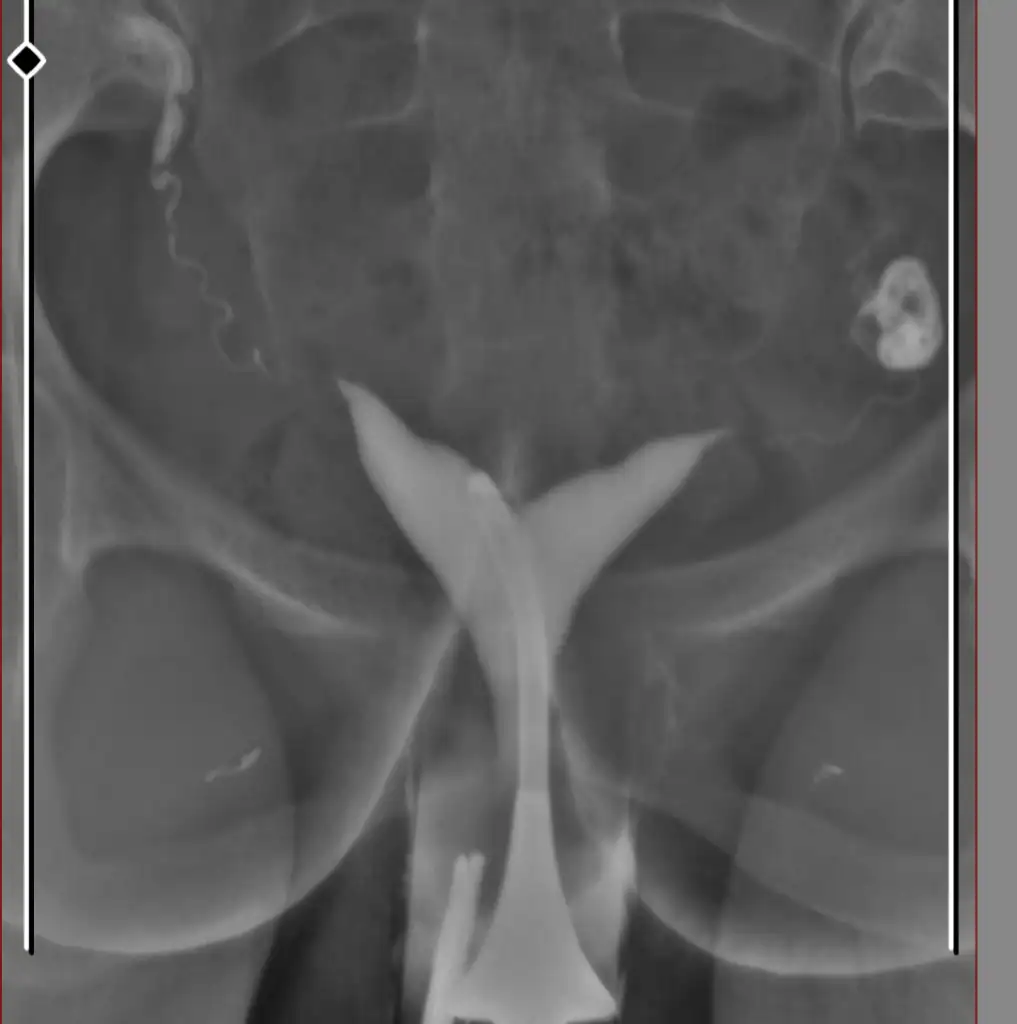

Histereskobi oncesi ve sonrası bu şekilde perde değil bircornis unicollis tanısı aldım doğuştan bu sekildeymis 2 düşüğüm var ne yapacağımı şaşırmış vaziyetteyim tekrar olmakta istemiyorumMerhaba ameliyat olmadım kendi doktorum kavite kötü değil olsa bırakmam dedi ameliyat ederdim üstten hafif basıklık var dedi bende kararsız kaldım bana bıraktı yinede olmadım çünkü doktorlar genelde rahime müdahale çok istemiyorlar bende böyle denemek istedim yeni bıraktım korunmayı bakalım progestanı artıracak birde yatacaksın 3 ay dedi o kadar bazı arkadaşlar sağolsun korkutmaya bayılıyorlar bu konuyu açtığımda bazıları kesin şöyle böyle diye yorum yapmıştı doktormuş gibi neyse bende doktorun dediğini söyledim size içinizi ferah tutun başka doktora görünün isterseniz bi perde mi vardı sizde film varsa atabilir misiniz

Sadece yanlardan mı genişletmişler sanki üstten basık görünüm devam ediyor yine siz bilirsiniz ama başka doktora kesin gösterin böyle doğuran çok insan var yarım rahimle bile varmış çok müdahale ettirmek iyi değil yapışıklık riski çok yüksek bicornis unicollis y rahim diye mi geçiyor acabaHistereskobi oncesi ve sonrası bu şekilde perde değil bircornis unicollis tanısı aldım doğuştan bu sekildeymis

Evet ben biraz fazla araştırdım diyr doktorum bana histerekopi videosu bile izletmişti. Sizin de alt kısım özellikle dar duruyor.Merhaba ya ben tekrar size sormak istedim üzerinden biraz zaman geçti ama bana baya y bu yazmıştınız neye göre öyle söylediniz daha önce rastladınız mı böyle bir rahim filmine yanlardan mı basık üstten mi merak ettimde

Daha önce özelde tüp bebek merkezine gittim dusuklerimi buna bağlamadı bu sekilde olup üçüz doguran bile var dedi mudahale edilmeyecek dedi sonra ünide doçente gittim laporoskobi yaptı üsten basık seninki dedi müdahale etmedi şimdi bi profa gidiyorum aslında oda ellemek istemedi ama yinede bi histeresmobi yapalim dedi 4 ay önce oldum şimdi rahim filminde biraz daha açsak iyi olur dedi çok az az müdahale ediyoruz o yüzden bu işlemlerde tekrarlama olabiliyor dedi aynı zamanda pcos var bende tedaviyr başlayacaktık artık ama böyle diyince ne yapacağımı şaşırdım doktor doktor gezmeninde pek bir anlamı yok gibi geliyor artık büyük ihtimal bir kez daha gebelik deneyeceğim yine düşük olursa müdahale ettirecegim suanki dusuncem bu yönde evet bu arada bicornis unicollis çift başlı rahim olarak geçiyor y şeklindeSadece yanlardan mı genişletmişler sanki üstten basık görünüm devam ediyor yine siz bilirsiniz ama başka doktora kesin gösterin böyle doğuran çok insan var yarım rahimle bile varmış çok müdahale ettirmek iyi değil yapışıklık riski çok yüksek bicornis unicollis y rahim diye mi geçiyor acaba

O çekim açısındanmış galibaEvet ben biraz fazla araştırdım diyr doktorum bana histerekopi videosu bile izletmişti. Sizin de alt kısım özellikle dar duruyor.